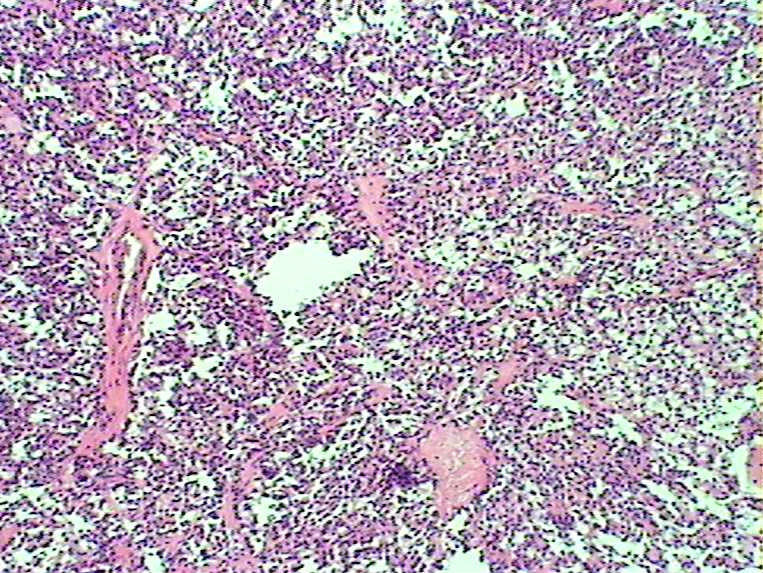

胰腺肿物 大体:灰白色肿物一枚大小:3*2*2cm,切面实性,质中。女,52

胰腺实性-假乳头状瘤

会诊实性假乳头状瘤